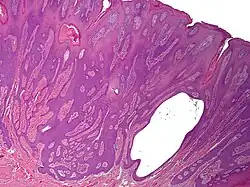

Syringofibroadenoma is a cutaneous condition characterized by a hyperkeratotic nodule or plaque involving the extremities.[1]: 668

It is considered of eccrine origin.[2]